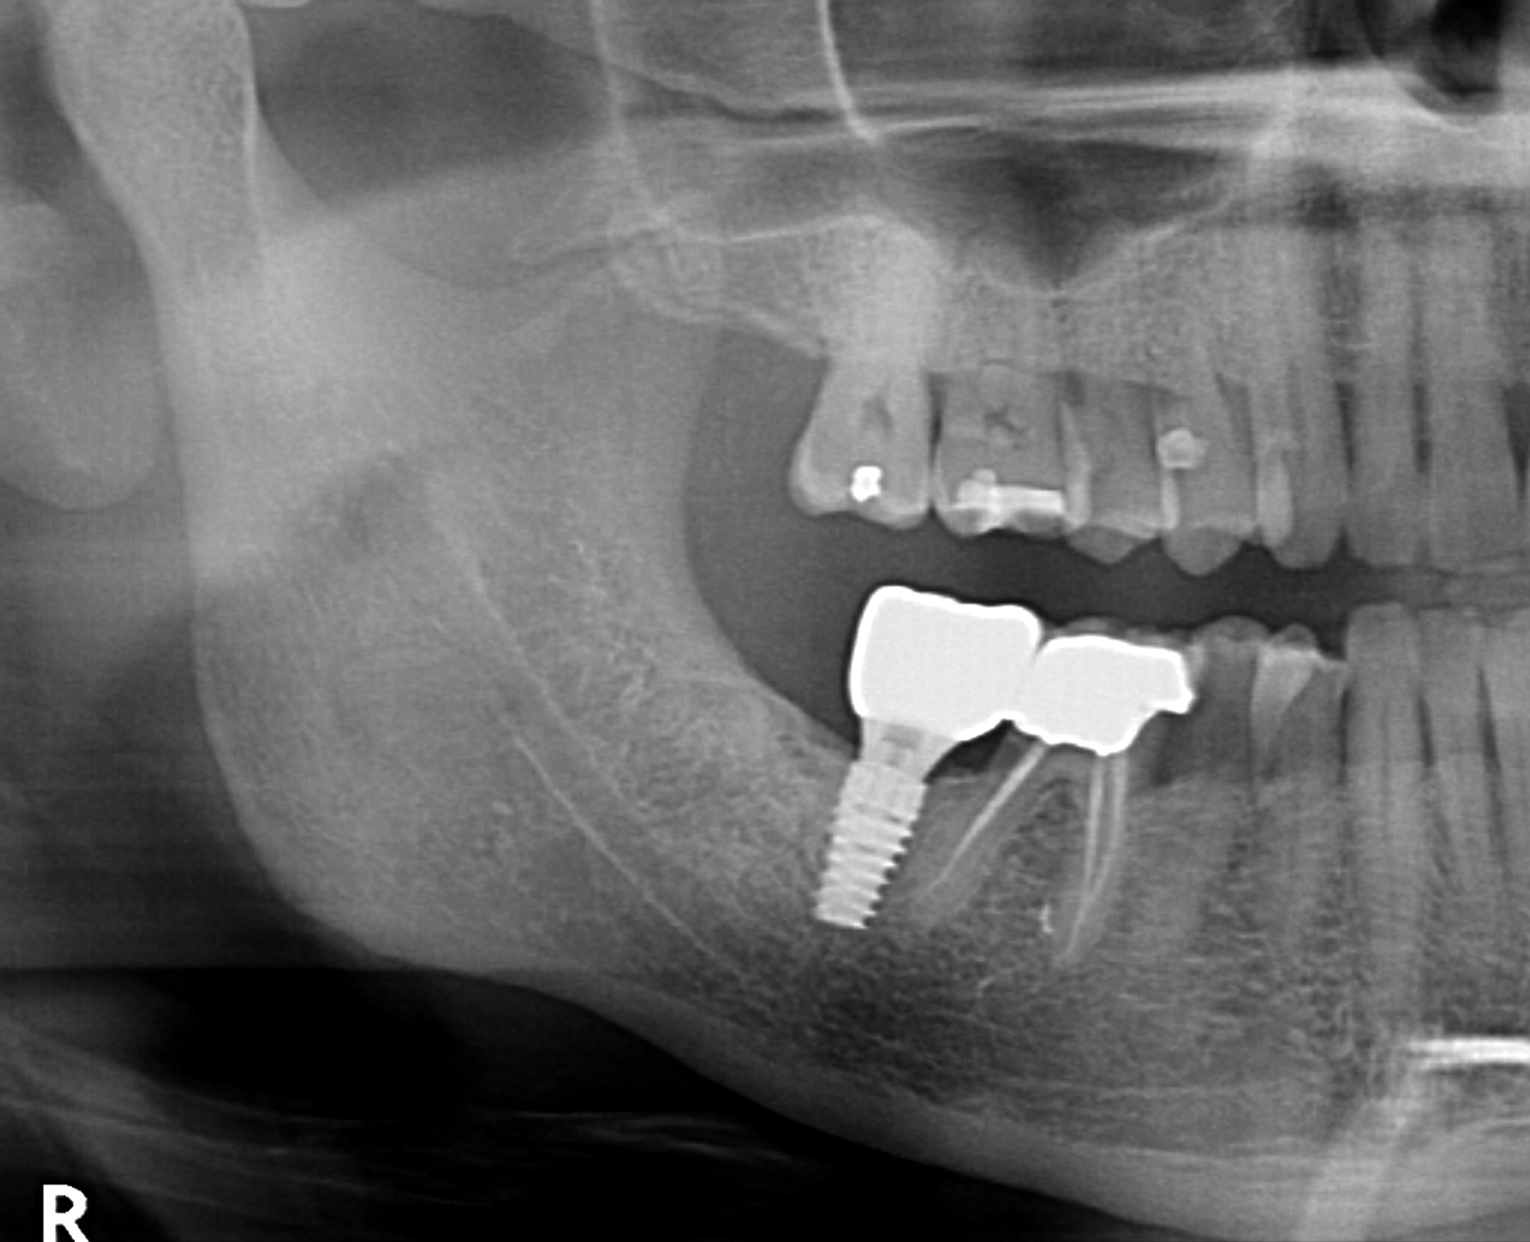

Healing of the site was observed on several occasions post-surgery, including at 4.5 months (Figure 18). Excellent gingival and underlying bone contours were revealed in 24-month photographs and panoramic x-ray (Figure 19 through Figure 21).

Fig 21. Panoramic image at 24 months restored.

Figure 21